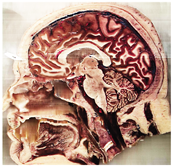

Table 2, Table 3, Table 4 and Table 5 present the results obtained through the multi-objective optimization image enhancement approach. Specifically, Table 2 and Table 3 show the results for natural images, while Table 4 and Table 5 display medical images. The tables are organized as follows: the first and second columns list the image names and their corresponding original, unenhanced versions. The third to fifth columns showcase the selected points from the Pareto front, representing the maximum contrast, knee point, and maximum detail, in that order. The final column illustrates the obtained Pareto front through the optimization process, with red, green, and orange points indicating the images that achieved maximum contrast, knee point, and maximum detail, respectively.

Table 4.

Medical image results—1.

As observed in the results, the images extracted from the Pareto front significantly maximize contrast and detail compared to the original images. In all study cases, the original image is dominated by the solutions extracted from the fronts, demonstrating the approach’s effectiveness in improving visual quality. However, the differences among the three enhanced images for each problem require a more detailed analysis.

For medical images, there are instances where differences are more perceptible. For example, in the Medical3 image, the maximum contrast solution makes it difficult to visualize the internal details of the basophil (a white blood cell highlighted in the box), which could result in a less accurate interpretation. In contrast, the knee and maximum detail solutions provide a clearer view of the interior of the white blood cell. Similarly, in the Medical5 image, the maximum contrast solution highlights the hand and arm bone structures. However, the maximum detail image offers a more precise view of the internal structures within the bones (see the highlighted region), which is crucial for a more detailed evaluation. Another notable example is the Medical8 image, where the maximum detail solution offers a more detailed view of the internal structure of the eosinophil (another type of white blood cell). However, the maximum contrast image improves the visibility of red blood cells. As shown in the yellow box, this solution reveals a red blood cell that is nearly imperceptible in the other solutions. An interesting case is the Medical6 image, where only a few non-dominated solutions are present on the Pareto front. Despite the similarities among the preferred solutions, the nodules are much more perceptible in the enhanced images than in the original image, as observed in the highlighted region.